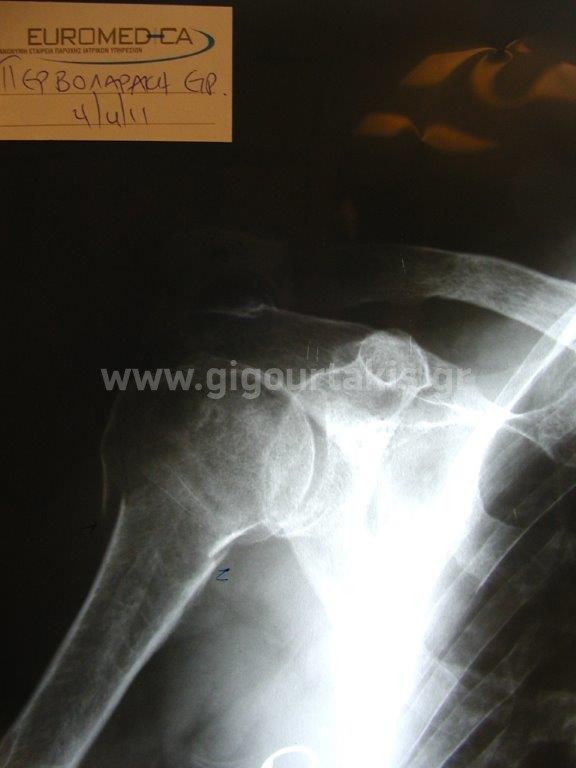

ΚΑΤΑΓΜΑ ΒΡΑΧΙΟΝΙΟΥ ΚΑΤΑΓΜΑ ΥΠΟΚΕΦΑΛΙΚΟ ΣΥΝΤΗΡΗΤΙΚΑ ΠΕΡΙΣΤΑΤΙΚΟ 1 01. 02. 03.ΑΡΧΙΚΗ ΑΠΑΓΩΓΗ ΩΜΟΥ 04.ΑΡΧΙΚΗ ΕΞΩ ΣΤΡΟΦΗ ΩΜΟΥ 06.ΑΡΧΙΚΗ ΕΣΩ ΣΤΡΟΦΗ ΩΜΟΥ 11.ΤΕΛΙΚΗ ΑΠΑΓΩΓΗ ΩΜΟΥ 12.ΤΕΛΙΚΗ ΟΠΙΣΘΙΑ ΠΡΟΣΑΓΩΓΗ ΩΜΟΥ 14.ΤΕΛΙΚΗ ΕΣΩ ΣΤΡΟΦΗ ΩΜΟΥ ΠΕΡΙΣΤΑΤΙΚΟ 2 01. 02. 04.ΑΡΧΙΚΗ ΑΠΑΓΩΓΗ ΒΡΑΧΙΟΝΙΟΥ 05.ΑΡΧΙΚΗ ΕΞΩ ΣΤΡΟΦΗ ΒΡΑΧΙΟΝΙΟΥ 06.ΑΡΧΙΚΗ ΟΠΙΣΘΙΑ ΠΡΟΣΑΓΩΓΗ ΒΡΑΧΙΟΝΙΟΥ 07.ΤΕΛΙΚΗ ΚΑΜΨΗ ΩΜΟΥ 2 08.ΤΕΛΙΚΗ ΑΠΑΓΩΓΗ ΩΜΟΥ 1 10.ΤΕΛΙΚΗ ΕΞΩ ΣΤΡΟΦΗ ΩΜΟΥ 2 11.ΤΕΛΙΚΗ ΟΠΙΣΘΙΑ ΠΡΟΣΑΓΩΓΗ ΩΜΟΥ 1 ΠΕΡΙΣΤΑΤΙΚΟ 3 01 Στις κατηγορίες:ΑΝΩ ΑΚΡΟ, ΣΥΝΤΗΡΗΤΙΚΑ, ΚΑΤΑΓΜΑ ΥΠΟΚΕΦΑΛΙΚΟ ΒΡΑΧΙΟΝΙΟΥ, ΚΑΤΑΓΜΑ ΒΡΑΧΙΟΝΙΟΥ, ΩΜΙΚΗ ΖΩΝΗ ΒΡΑΧΙΟΝΙΟ, ΚΑΤΑΓΜΑTA